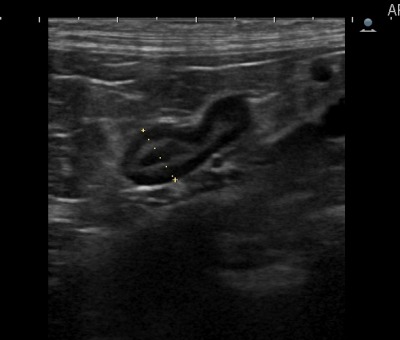

↑当院でのエコー画像。クッシング診断にあたり左右の副腎の大きさ・形態は必ずエコーでチェックします。mm単位のこんなに小さな臓器が非常に重要な役割をしています。「小さな巨人」と言われるのにも納得です。ももクロの緑だった人のようです。